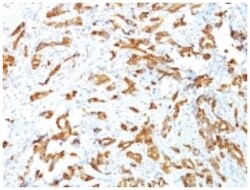

HSP27 Monoclonal specifically detects HSP27 in Human, Mouse, Rat, Chicken, Chimpanzee, Monkey, Sheep samples. It is validated for Western Blot, Flow Cytometry, Immunohistochemistry, Immunocytochemistry/Immunofluorescence, Immunohistochemistry-Paraffin.Specifications

| This MAb reacts specifically with heat shock protein HSP27 in human and monkey tissues and cell lines such as MCF-7. HSP27, also referred to as the Estrogen-Regulated 24K protein and HSP28, is one of several small heat shock proteins produced by all organisms studied. HSP27 synthesis is induced by elevated temperature, as well as by estrogen in hormone responsive cells. Interestingly, human HSP27 also shares greater than 50% homology with low molecular weight Drosophila HSPs and mammalian alpha-crystalline lens protein. Because of the estrogen responsive nature of HSP27, this protein has been studied extensively in human estrogen responsive tissues such as cervix, endometrium and breast tissue. Therefore HSP27 may be useful in classifying various hormone sensitive tumors. |